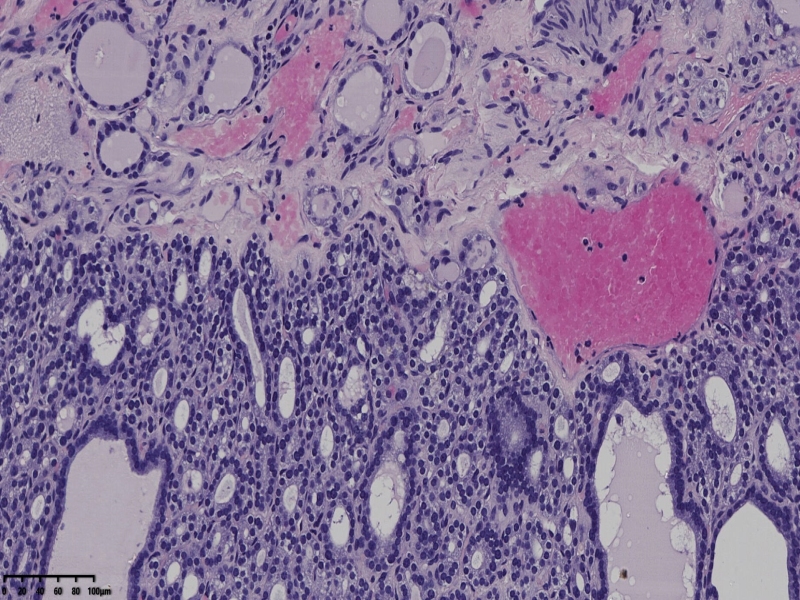

男、69、甲状腺左叶肿物,部分为囊性,囊内可见乳头状结构,上皮核重叠,没有核沟,没有毛玻璃样改变,没有核内假包涵体。255427

部分区域瘤组织与周围甲状腺组织分界明显,没有包膜样结构,滤泡结构为主,细胞异型明显。

会诊结果:(左叶甲状腺近峡部)甲状腺肿瘤,考虑为具有RAS核的乳头状癌,建议免疫组化及基因检测。